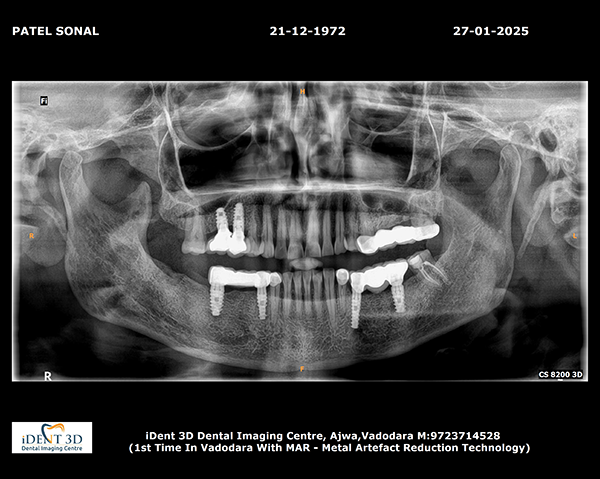

Guided Implant Surgery involves the use of advanced 3D imaging and computer-aided design (CAD) to plan the exact placement of dental implants. This meticulous planning process allows our dental specialists to visualize the patient’s oral anatomy in great detail, ensuring the implants are placed in the most ideal position for both functionality and aesthetics. The procedure is tailored to each patient's unique needs, ensuring a personalized treatment plan.

These technique assures that the implant is precisely placed without any damage to nerves, vessels and wouldn't perforate maxillary sinus too.